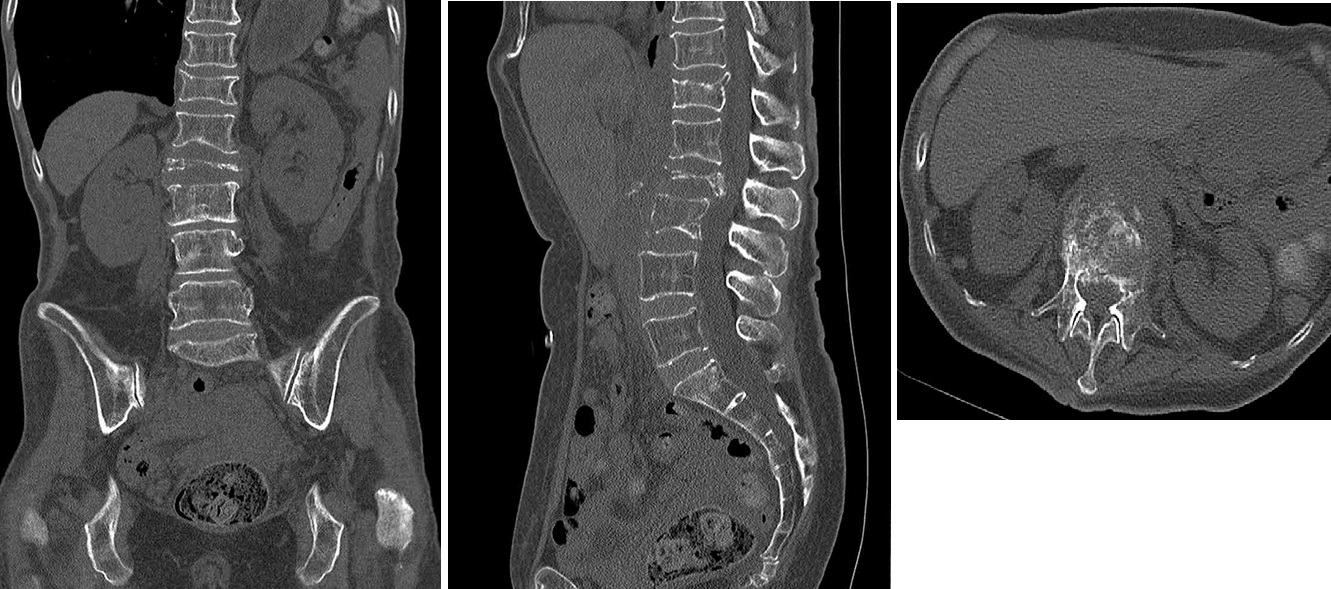

代表的な癌性疼痛として、骨転移に関しては、椎体形成術(骨セメント)やTAEが有効です。また、骨以外でも、腹壁転移による痛みや腫瘍浸潤による痛みで、安全なfeederが確保出来る場合はTAEの適応です。また、内臓神経/腹腔神経叢ブロックも可能です。

椎体形成術(PVP, 骨セメント)

骨 TAE